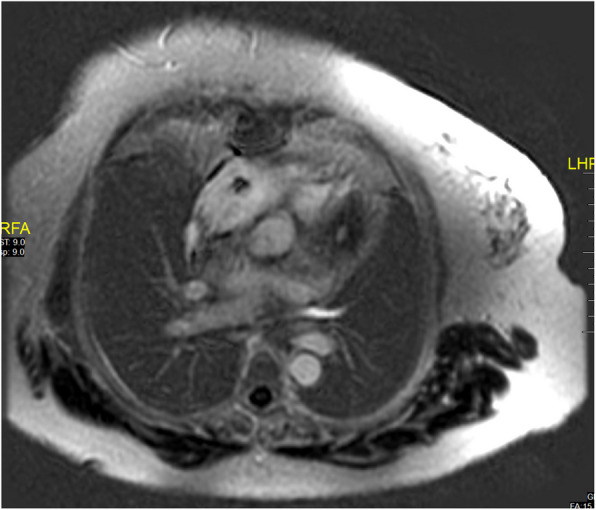

Very low-dose vemurafenib maintenance for cardiac Erdheim Chester disease.

Abstract Image